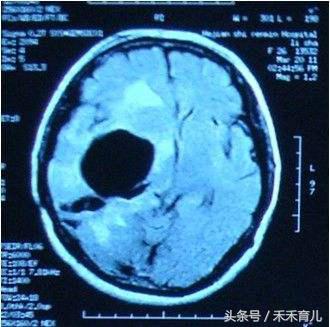

首先给大家说下脑侧室增宽的定义:侧脑室宽度是预测胎儿神经系统功能的一项重要指标,因此是产前系统超声检查的常规项目;在妊娠16-38周内,正常的侧脑室宽度一般为7.6mm±0.6mm,当胎儿侧脑室体部宽度达10~15mm,称为轻度侧脑室增宽,在中晚孕期发生率约1%;若胎儿轻度侧脑室增宽未合并其他任何结构异常时则称为孤立性轻度侧脑室增宽;若侧脑室宽度超过15mm则为胎儿脑积水;约60%的病例为单侧轻度侧脑室增宽,约40%的病例为双侧轻度侧脑室增宽。

3、15毫米以上,重度侧脑室增宽。而这种重度侧脑室增宽,就是我们白话说的脑积水。

因为侧脑室增宽有轻度、中度、重度之分,因此孩子的恢复情况也不一样。现在我们倾向于将10~12毫米的侧脑室增宽叫做临界增宽。现在发现80%以上有轻度侧脑室增宽的胎儿,出生之后是正常的。 但也有一些轻度增宽的胎儿定期检查发现,侧脑室的宽度在逐渐增加,比如这次查11~12毫米,2~3周再查时发展到13~14毫米了,再复查发现变成14~15毫米。这种情况可能预示着孩子出生之后存在神经系统和智力的损伤。 当然,无论是逐渐增宽到15毫米以上,还是第一次检查就在15毫米以上,最后的恢复都是比较差的。如果大脑里的水多了,可供大脑发育的空间也就相应减少。所以如果侧脑室达到15毫米以上的脑积水标准,就会把脑子压得比较扁,进而对孩子的神经发育造成影响。